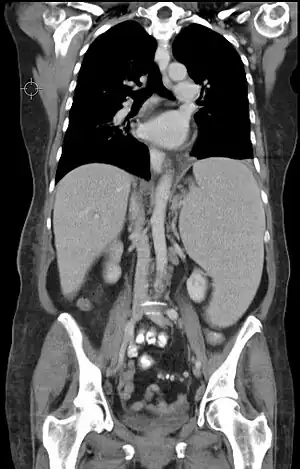

Leucemia é um grupo de cancros que surgem geralmente na medula óssea e causam um número elevado de glóbulos brancos anormais.[7] Estes glóbulos brancos não estão totalmente desenvolvidos e são denominados células leucémicas.[1] Os sintomas incluem hemorragias e contusões, fadiga, febre e aumento do risco de infeções,[1] e podem ocorrer devido à ausência de células sanguíneas normais. O diagnóstico é geralmente feito através de análises ao sangue ou biópsia da medula óssea.[1]

Diagnóstico

- Hemograma: ao fazer um exame de rotina, pode-se notar um hemograma anormal sugestivo de leucemia com presença de células imaturas ou uma proliferação excessiva de células aparentemente maduras. O hemograma não serve para classificar a leucemia, mas geralmente é o primeiro exame a ser notado alguma alteração. Também se verifica se há presença de anemia e trombocitopenia.

- Mielograma: É um exame de grande importância para o diagnóstico, através da análise da morfologia das células e com o uso de provas citoquímicas. O mielograma é usado também para a avaliação da resposta ao tratamento, indicando se, morfologicamente, essas células leucêmicas foram erradicadas da medula óssea (remissão completa medular). Esse exame é feito sob anestesia local e consiste na aspiração da medula óssea seguida da confecção de esfregaços em lâminas de vidro, para exame ao microscópio. Os locais preferidos para a aspiração são a parte posterior do osso ilíaco (bacia) e o esterno (parte superior do peito). Durante o tratamento são feitos vários mielogramas.